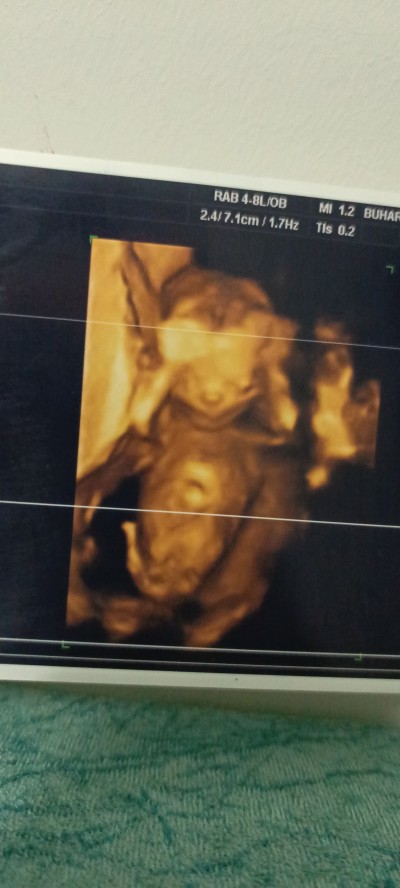

Kızlar ben 15 haftalık hamileyim cinsiyet tahmını olan varmı acaba

Gebelik haftası 15

Kız gibi geldi canm

Doktor da öyle dedi ama erken ya ben bide bırdan sorayım dedım teşekkür ederim canım sağol